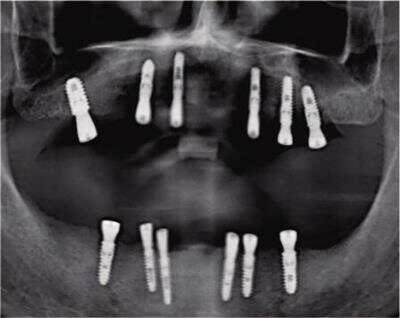

▲梁叔即刻种植12颗修复全口牙 |